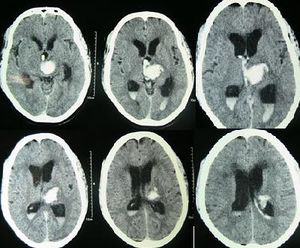

يتم التعرف على النزف الدماغي عن طريق التصوير المقطعي المحوسب حيث تظهر الدماء أكثر أفتح عن الأنسجة ويفصلها عن الجدار الداخلي للجمجمة نسيج الدماغ. الأنسجة المحيطة بالدماء عادة ما تكون أقل كثافة عن بقية الدماغ بسبب الوذمة، ومن ثم فيظهر أفتح في التصوير المطقعي المحوسب.